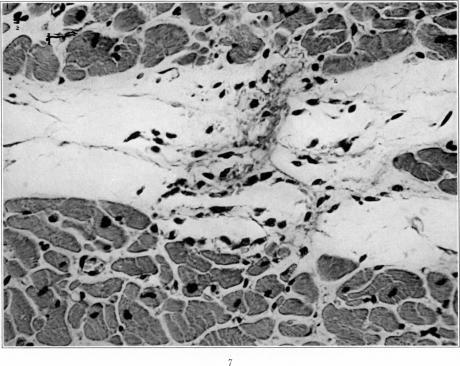

Studies on the Myocardial Aschoff Body: I. Descriptive Classification of Lesions.

Am J Pathol. 1934 Jul;10(4):467-488.15.

Studies on the Myocardial Aschoff Body: I. Descriptive Classification of Lesions.心肌阿绍夫小体的研究:I. 病变的描述性分类